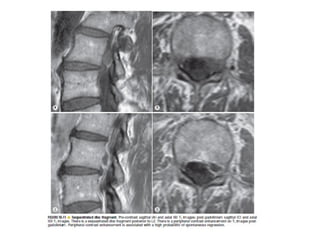

The spine is made up of vertebrae separated by intervertebral discs that allow movement and provide shock absorption. Diagnostic imaging plays an important role in evaluating the spine for conditions like fractures, disc herniations, spinal stenosis, and tumors. Imaging modalities like X-rays, CT scans, MRI, and bone scans can detect abnormalities and aid physicians in diagnosing and treating various spinal disorders.